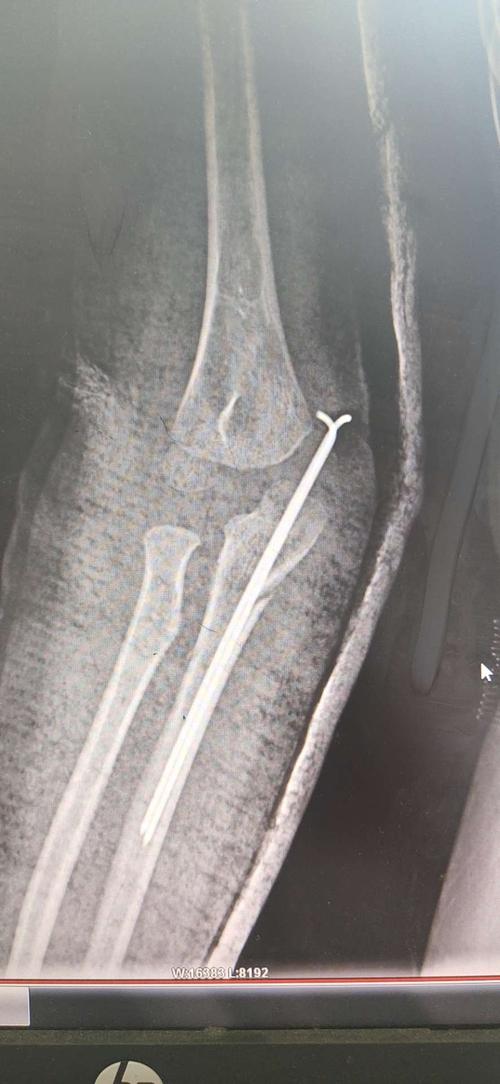

病例1 3型孟氏骨折,拟闭合复位克氏针固定.

一例复杂性类孟氏骨折闭合复位弹性髓内钉内固定病例分享